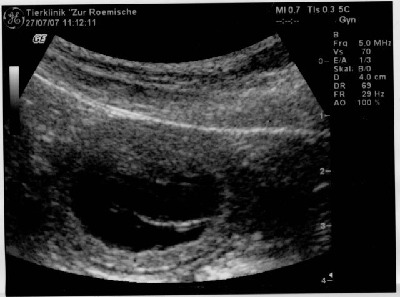

Am 27.07.07 bestätigte die tierärztliche Ultraschall-Untersuchung Ambrosias Trächtigkeit.